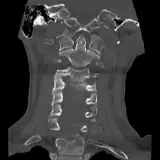

Des cas entièrement interactifs avec les outils attendus d'un PACS — défilement, fenêtrage, zoom, déplacement, mesures, ROI et mode plein écran.

Des annotations détaillées mettent en évidence les résultats clés directement sur les cas. Cliquez sur les résultats liés dans les descriptions de cas pour accéder à leur emplacement exact sur l'examen.

Défilez, déplacez, fenêtrez et zoomez comme sur une station PACS de travail